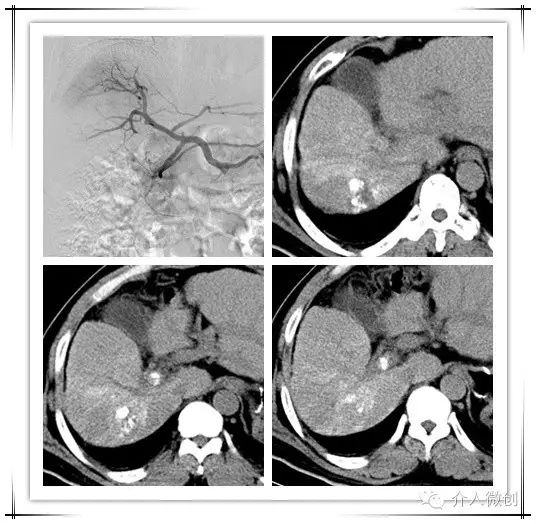

中年男性,诊断为原发性肝癌并门脉右支癌栓,术前甲胎蛋白升高(AFP:484ug/ml)。先予以行肝动脉化疗栓塞术(TACE),术后复查CT提示肝内病灶部分碘油沉积,门脉右支癌栓亦可见碘油沉积。

肝动脉化疗栓塞术

术前术后影像对比

针对病灶碘油沉积欠缺情况,予以行CT引导下射频消融,治疗后病灶中心出现气化。